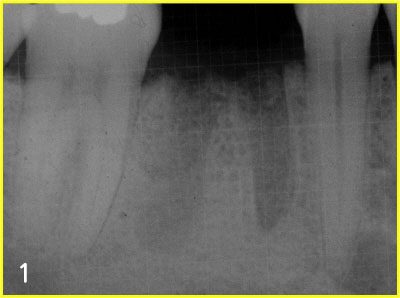

Set up surgical plan with x-ray

Placing implant

taking X-ray to secure safe implant surgery